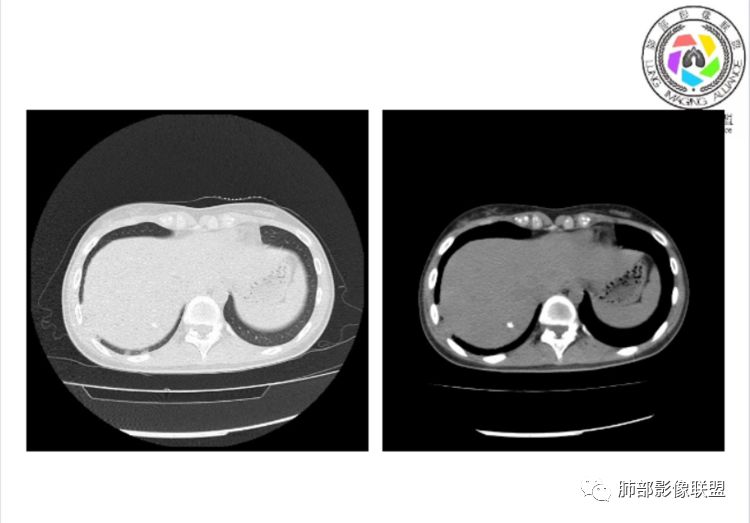

小微:右肺下叶斑片状密度增高影,抗炎治疗6天后复查,双肺下叶出现斑片状密度增高影,排除炎性病变,D2聚体特别高,考虑肺栓塞,肺梗死,建议增强扫描。王开金江津中心医院呼吸科:@岳微-辽宁PLA234医院放射科?支持,患者年轻女性,胸痛主诉,使用雌激素,高危人群,心率快,d二聚体升高,右下叶斑片加肺动脉明显增宽,抗感染无效,要考虑PTE,建议肺动脉ctpa。傅昌瑜:19岁,女性,右侧胸痛2天,发热以中度热为主,D—二聚体升高,肺动脉主干增宽,病灶位于胸膜下,抗感染后增多,近来有服用炔雌醇环丙孕酮片2周期史,诊断:肺栓塞,下一步完善肺CTPA检查。阿仙奴:青年女性,急性起病,胸痛入院,月经不调史,目前服用孕酮片。流感抗体阳性,d二聚体升高,无低氧血症。右肺下叶基底段胸膜下磨玻璃样改变,肺动脉增宽,治疗过程出现发热,复查左下叶胸膜下新发病灶。考虑:肺栓塞(服用孕酮相关)?奔跑的37°Doctor(陆喜红 ) :年轻女性,胸痛 急性病程,有服用雌激素避孕药史(是否有血液循环的改变,高凝状态),实验室D二聚体很高(也是提示血液高凝状态) ,第一次CT,右下肺胸膜下斑片状密度增高模糊影,肺动脉形态密度未见明显异常,抗炎后复查,肺动脉干及其分支,感觉增粗了一点,局部形态有点饱满,双下肺胸膜下片状影增多,锁定肺动脉栓塞应该不会错,建议CTA检查飞鹰行动:青年人,女性,右肺下叶斑片状密度增高影,抗炎治疗6天后复查无好转,,双肺下叶出现斑片磨玻璃影,主肺动脉增粗,结合患者服用的药物和D2聚体特别高,考虑肺栓塞,建议CTA。李:口服避孕药,有危险因素,肺动脉较主动脉增宽,D二聚体增高,胸膜下片状影,考虑肺栓塞;@晨义工张帅,医附属潞河医院呼吸?是否痰中带血很关键,不知有没有张帅:患者入院后第七天出现痰中带血风之子:病程中有发热,D—二聚体升高,肺动脉主干增宽,病灶分布于胸膜下,抗感染后增多,结合服药史诊断:肺栓塞,建议CTPA检查。不支持的地方是没有低氧血症,不明白为什么第二次复查ct双侧乳腺不对称,按理乳腺炎多见于哺乳期张帅:大家方向都在考虑肺栓塞:我提问两个问题:1 周围毛玻璃怎么回事?2左下肺小叶间隔增宽怎么回事?笨丫头:周围的磨玻璃应该考虑是肺梗死后出血渗出,同时合并机化性炎症小叶间隔增宽,我考虑应该是梗死后炎性渗出wonderful:我不支持肺栓塞 不能解释发热原因

水晶石头:患者青少年女性,右侧胸痛2天就诊。有咳嗽,无痰。初次胸部CT:右下肺片状模糊影。入院后经头孢美唑、莫西沙星抗感染治疗6天后复查胸部CT:右下肺病灶加重,且左下肺出现类似病灶。结合其气管镜气道无异常,病程中有发热,D—二聚体升高,近来因月经不调有服用炔雌醇环丙孕酮片史。诊断考虑良性非感染性。肺栓塞可能性大,鉴别血管炎及子宫内膜肺异位可能。流心明智:女性,19岁,右侧胸痛2天,中度热为主,D—二聚体升高,影像:肺动脉主干小于29mm,病灶位于右下肺胸膜下,斑片影,胸膜侧宽基底,抗感染后增多,左下肺亦出現类似病灶,似有反晕、融冰征。近来有服用炔雌醇环丙孕酮片2周病史,考虑诊断:肺栓塞。具体性质及发病机制有待进一步检查。尘缘:@吴永丽 灌云县医院 呼吸?应该是的,左下肺的磨玻璃影像后面也支持有出血改变所以可能就是一个子宫内膜异位出血合并感染

1、一个或多个胸膜下斑片高密度影(梗死、出血、肺不张、肺水肿、炎性渗出),典型为胸膜下楔形影 ,尖端指向肺门

2、肺动脉高压(中心肺动脉扩张),有时可见肺动脉区高密度影。

3、肺血减少

3.影像:病变胸膜下多发斑片影,提示与血管有关,早期病变为渗出,应该是早期的炎性渗出,病灶抗感染治疗后实变区增多、变大,临床症状又出现咯血,CT上应该合并了肺泡出血、梗死、肺不张及肺水肿;